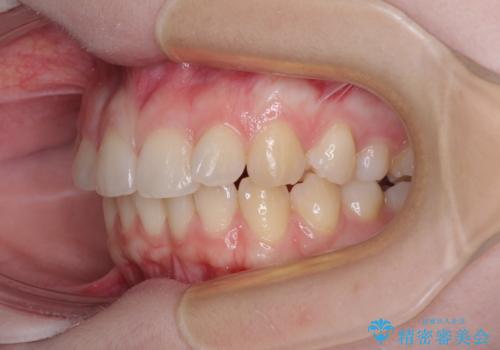

左上の前歯が出ているのが気になる 審美装置による非抜歯ワイヤー矯正

- 左上の前歯が出ていることを主訴として来院された患者様です。

当初はインビザラインを希望されていましたが、職業柄お茶する機会が多く装着時間を確保することが難しいとのことで、相談の上ワイヤー矯正の中では目立ちにくい審美装置で矯正を進めていくこととしました。